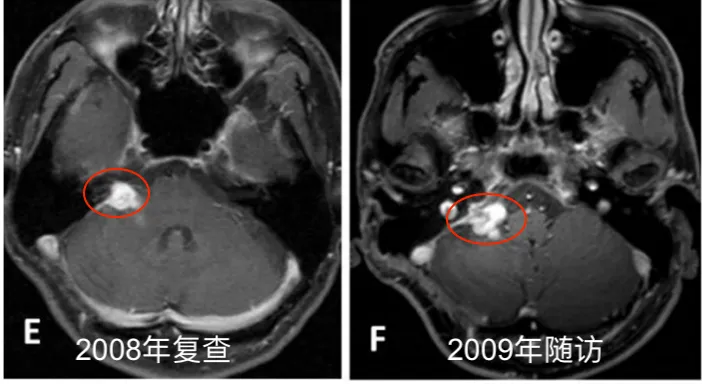

此后长达6年时间,患者坚持每半年进行一次MRI随访,残余肿瘤体积保持稳定。直至2013年11月,常规随访影像显示肿瘤重新出现生长迹象。2014年4月,患者出现进行性头痛、眩晕、恶心等症状,影像学证实肿瘤体积明显增大,并伴有脑干受压表现。